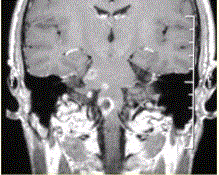

问题 患者男,35岁,肢体无力半年。头部MRI显示如下图。 患者的下一步治疗包括

选项 A.免疫抑制剂及激素 B.降颅压 C.抗炎 D.抗血栓 E.无须特殊治疗

答案 A